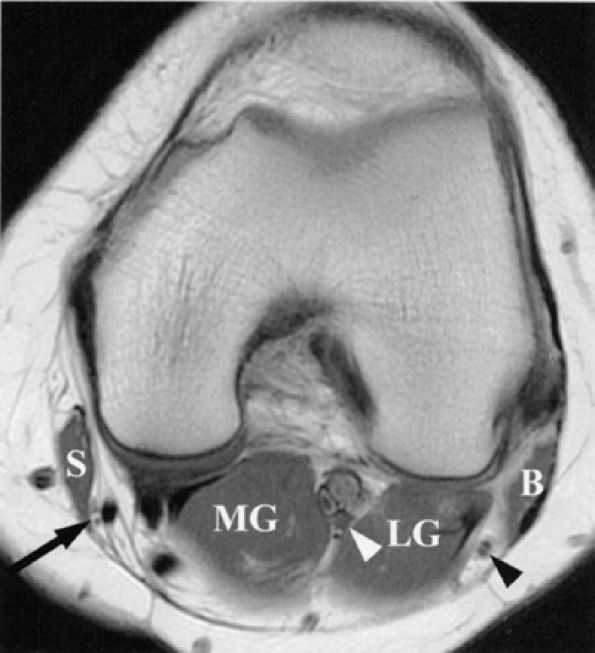

FIGURE 6.21 ● Normal saphenous, tibial, and common peroneal nerves in the knee. An axial PD-weighted image depicts the branches of the saphenous nerve (arrow) lateral to the sartorius muscle (S); the tibial nerve (white arrowhead) between the lateral (LG) and medial (MG) heads of the gastrocnemius muscle; and the common peroneal nerve (black arrowhead) between the gastrocnemius muscle and biceps femoris muscle (B). Note that the common peroneal nerve is already split into its deep and superficial branches.

|